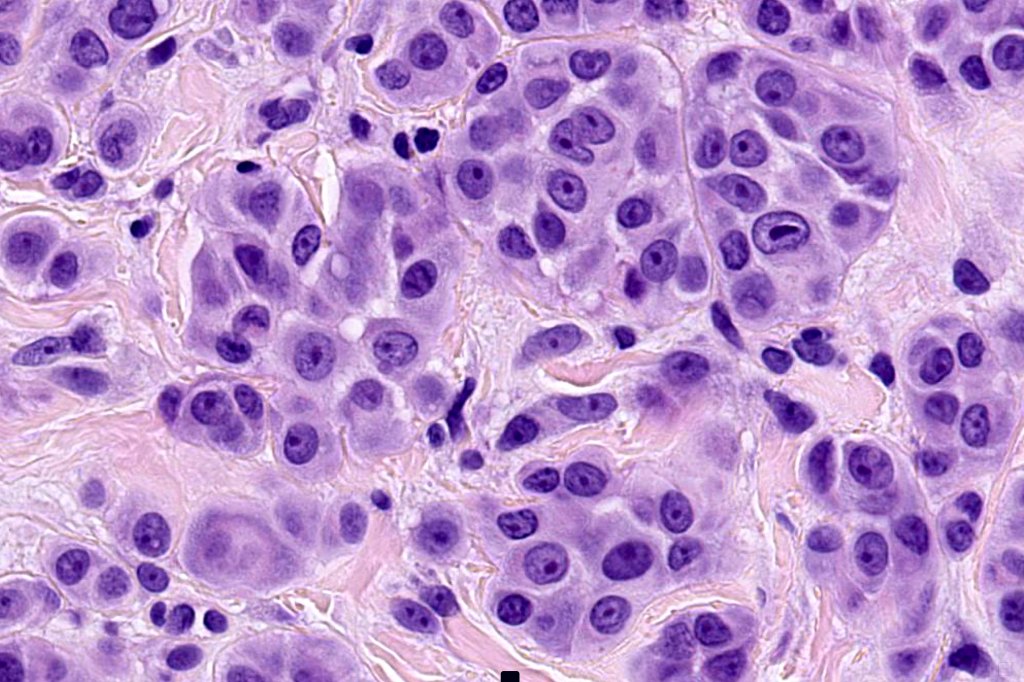

Histological features

•>5-10 mm

•Involve deep dermis or subcutis

•Asymmetrical, poorly circumscribed

•May show effacement/consumption of epidermis or ulceration

•Peripheral Pagetoid spread

•Large nodules which often show impaired maturation

•Loss of gradient with HMB45 and Ki67

•>20% Ki67 expression

•TERT promoter & PTEN mutations

•DNA copy-number variations